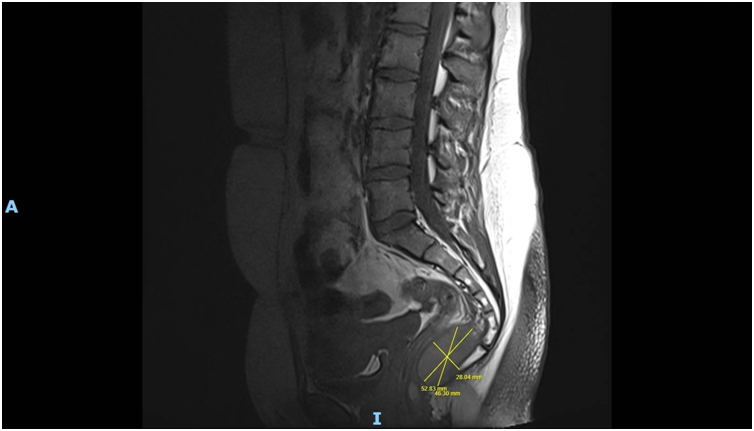

Imaging via MRI and CT demonstrated a complex, encapsulated lesion with peripheral enhancement and restricted diffusion. Multidisciplinary evaluation suggested a congenital epidermoid or duplication cyst. Given the absence of malignancy and surgical complexity, a conservative management strategy was adopted.

Figure 1: Figure 1 Duplication cyst 2025 MRI sagittal plane

Figure 2: Figure 2 Duplication cyst 2025 MRI sagittal plane

Figure 6: Figure 6 Duplication cyst 2025 sagittal plane